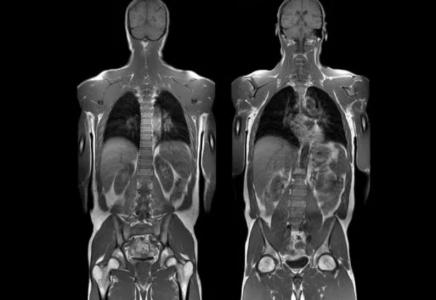

Магнитно-резонансная томография - высокоинформативная диагностическая процедура, с помощью которой получают послойные изображения органов, внутренних структур, костно-суставного аппарата без инвазивного проникновения в человеческое тело. МРТ показывает даже незначительные отклонения от нормы. При необходимости множество срезов заданной толщины компьютерная программа преобразовывает в единое объемное изображение. Доктор может рассматривать патологический очаг на экране монитора в увеличенном виде в разных проекциях, с помощью определенного режима убрать “лишние” структуры.

С помощью магнитно-резонансной томографии можно выявить заболевания головного и спинного мозга, органов грудной клетки, ретроперитонеального пространства, брюшной полости, малого таза.